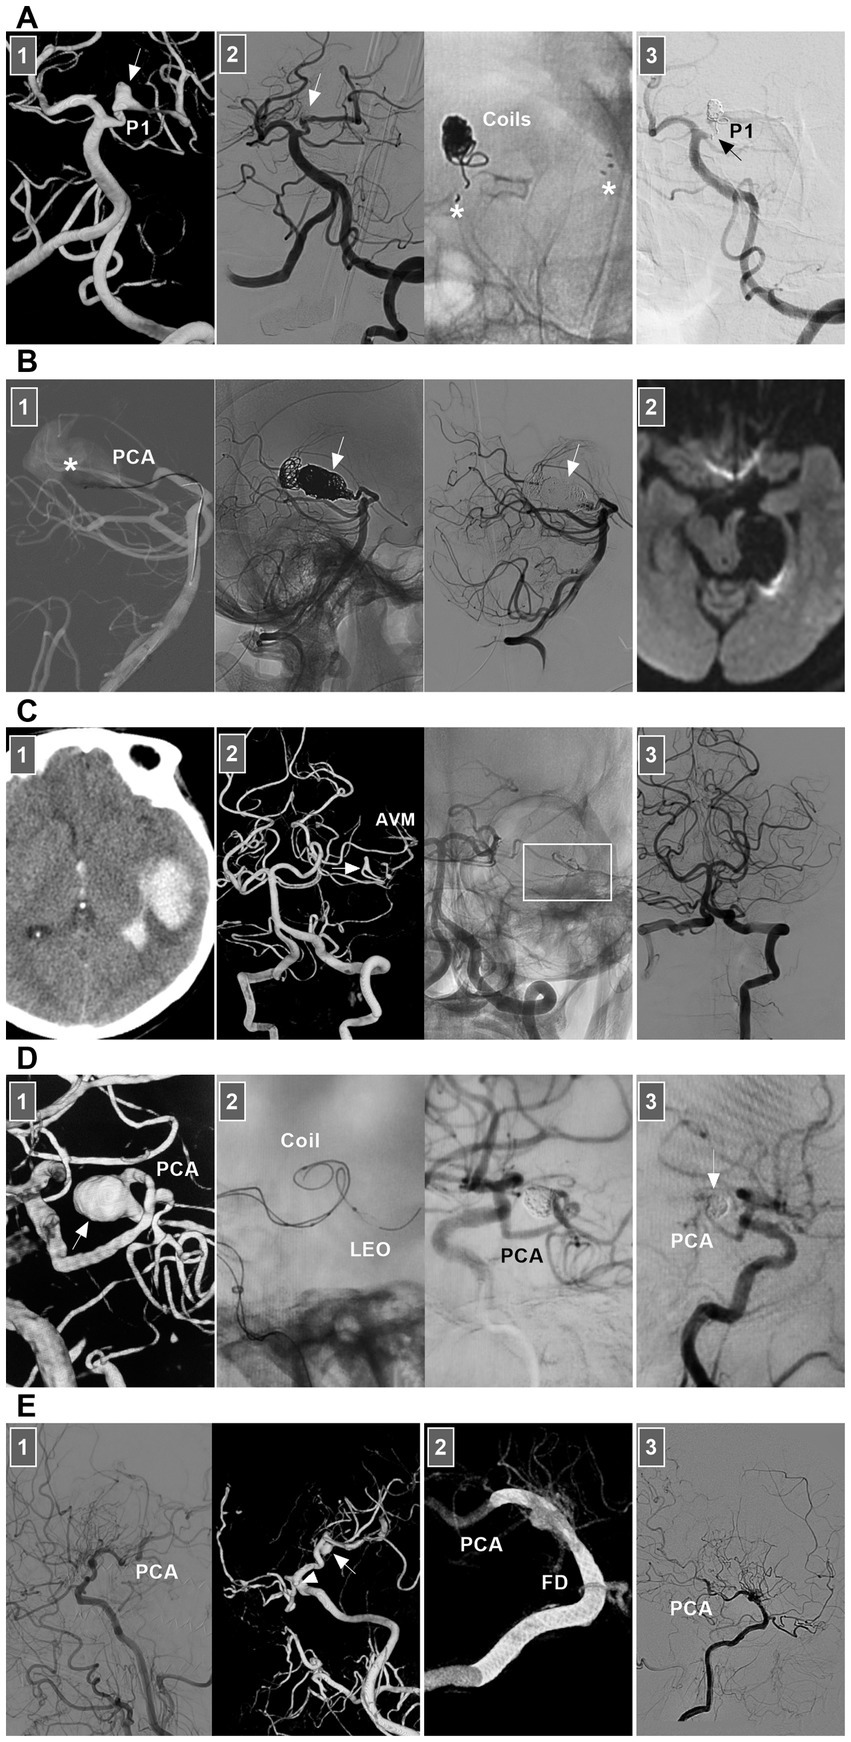

8.2.3 PCA dissection

PCA dissections are uncommon (84). They can present with ischemic symptoms in the PCA territory, mass effects, or SAH (84). For ischemic lesions, even occluded PCAs, conservative anticoagulation management can be chosen, and EVT should not be routinely recommended (85–87). For acute ruptured PCA dissections or chronic symptomatic dissections, EVT may be necessary (88). Both reconstructive and deconstructive EVT can be used. Deconstructive EVT is relatively safe even in the absence of a BOT due to rich collaterals, which especially benefit critically ill patients with ruptured PCA dissecting aneurysms or cases of difficult access or financial constraints.

For P1 and P1–P2 junction dissections, because of the presence of thalamic perforating arteries, acute occlusion of the proximal PCA can be life-threatening (89). However, chronic occlusion was safe (Figure 12A). The potential collateral supply and hemodynamic balance between the anterior and posterior choroidal arteries, pericallosal vessels, and ACA and MCA to the distal PCA make P2 occlusion safe (90, 91). The P2 segment of the fetal-type PCA can send out more perforating arteries, and anastomosis between the MCA and PCA tends to result in less development of collaterals (92). At this time, PAO should be performed cautiously. Owing to the rich collateral circulation, PAO of aneurysms in the P3–P4 segment can be performed (Figure 12B) (88, 93, 94). For PCA flow-related aneurysms, reconstructive EVT is often difficult, and PAO can be performed (Figure 12C). However, PAO is associated with a nonnegligible rate of complications, even though most are minor events such as hemianopsia (95).

Figure 12

EVT of PCA dissections. (A) Panel 1: DSA showing a P1 dissection (arrow). Panel 2: DSA (left panel) showing that the dissection (arrow) was coiled by stent assistance, and X-ray image (right panel) showing the coils and stent (asterisks). Panel 3: Six-month follow-up DSA showing that the P1 segment of the PCA was nearly occluded (arrow). (B) Panel 1: X-ray image (left panel) showing the microcatheter went into the giant distal PCA dissection aneurysm (asterisk) to wait for the coiling, DSA and unsubtracted DSA (middle and right panels) images showing the aneurysm (arrows) and the parent PCA were occluded. Panel 2: Diffuse weighted image of magnetic resonance showing no ischemia of PCA region. (C) Panel 1: CT showing left temporal hemorrhage. Panel 2: DSA (left panel) showing an AVM supplied by the branch of PCA with a flow-related dissecting aneurysm (arrow), and unsubtracted DSA (right panel) showing the dissection was embolized by casting Onyx (frame). Panel 3: DSA showing the AVM was obliterated. (D) Panel 1: DSA showing a sidewall dissecting aneurysm (arrow) of distal PCA. Panel 2: X-ray image (left panel) showing the design of the EVT by LEO stent assisted-coiling, and DSA (right panel) showing the aneurysm was embolized. Panel 3: Six-month follow-up DSA showing the aneurysm (arrow) had no recurrence. (E) Panel 1: DSA (left panel) showing the moyamoya disease and well-developed PCA, and DSA (right panel) showing a distal PCA dissecting aneurysm and an ophthalmic aneurysm (arrowhead). Panel 2: Vaso-reconstructive image showing that the FD covered two aneurysms. Panel 3: DSA showing the PCA was patent. AVM, arteriovenous malformation; CT, computed tomography; DSA, digital subtraction angiography; EVT, endovascular treatment; FD, flow diverter; PCA, posterior cerebral artery; P1, first segment of PCA.

Compared with deconstructive EVT, reconstructive EVT is promising because current new devices have good clinical and safety profiles (91). In a report by Tang et al. (96) in 2022, braided stent-assisted coiling resulted in a high occlusion rate and a relatively low complication rate in treating PCA dissecting aneurysms. In addition to braided stents such as LVIS (Microvention, Tustin, California, United States) and LEO stents (Balt, Montmorency, France) (Figure 12D), FDs have revolutionized EVT for dissections (Figure 12E). However, FD deployment for PCA dissection is fraught with the risk of thromboembolic complications owing to side branch coverage by the FD (96).

8.2.5 AICA dissection

For ruptured AICA dissections with a risk of rebleeding or flow-related dissection with AVMs, EVT may be suggested. The AICA is a small artery that can be divided into the a1–a4 segments (104, 105). The proximal a1 segment sends off brainstem perforators, and the a2 segment sends off the internal auditory artery. Proximal PAO can result in brainstem infarction and hearing loss, and it is the last resort (104, 106). Reconstructive EVT was the preferred choice. Owing to the limitation of the AICA diameter, stenting in the AICA can be employed only for a thick AICA or the common trunk of the AICA-PICA (107). For example, in 2024, Kass-Hout et al. (108) treated AICA dissection with FD [a silk vista baby device (Balt, Montmorency, France)]. PAO is acceptable for distal AICA dissections (Figure 13A).

Figure 13

EVT of AICA and PICA dissections. (A) Left panel: DSA showing a ruptured AICA dissection (arrow). Middle panel: Unsubtracted DSA showing the dissection (arrow) was coiled. Right panel: DSA showing the AICA was patent, and chronic occlusion was worthy to expected. (B) Left panel: CT showing SAH. Middle panel: DSA showing a ruptured PCA sidewall dissecting aneurysm (arrow). Right panel: DSA showing the aneurysms (arrow) was coiled selectively. (C) Panel 1: CT showing the fourth ventricle hemorrhage. Panel 2: DSA (left panel) and its reconstructive image (right panel) showing an AVM that supplied by PICA with flow-related dissecting aneurysms (arrows). Panel 3: DSA (left panel) showing the aneurysms were embolized (arrow), unsubtracted DSA (right panel) showing the Onyx in the aneurysm. Panel 4: Diffuse weighted image of magnetic resonance showing asymptomatic acute ischemia of cerebellar hemisphere. AICA, anterior inferior cerebellar artery; AVM, arteriovenous malformation; CT, computed tomography; DSA, digital subtraction angiography; EVT, endovascular treatment; PICA, posterior inferior cerebellar artery; SAH, subarachnoid hemorrhage; VA, vertebral artery.

8.2.6 PICA

For unruptured PICA dissections, conservative treatment can be recommended for those without obvious angiographic risk factors for hemorrhage, such as pseudoaneurysm (109). However, for ruptured PICA dissections with a high risk of rebleeding, recurrence, or flow-related AVM, EVT may be suggested (Figures 13B,C). Ideal EVT comprises complete embolization of the PICA dissections while preserving the PICA and perforating arteries (110–112). However, reconstructive EVT is difficult to perform because the diameter of the PICA trunk is not thick. Therefore, PAO had to be employed.